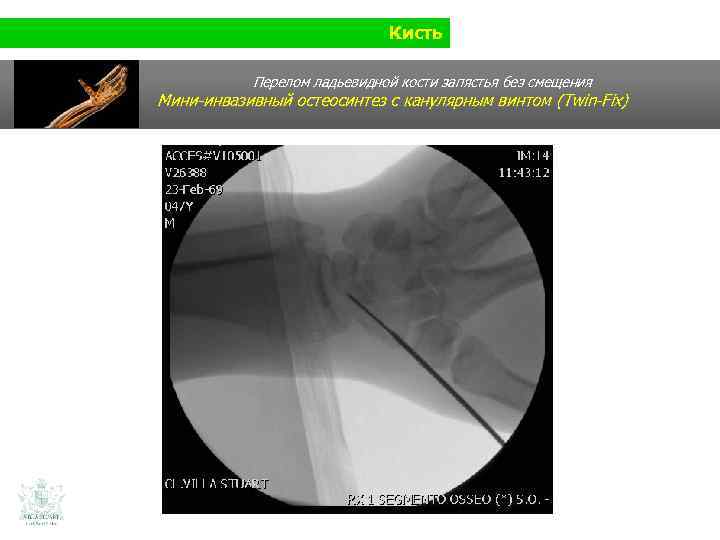

Кисть Клинический случай (кисть) Мужчина 35 лет Падение на ладонь (при защитной реакции)

Кисть Перелом ладьевидной кости запястья без смещения

Кисть Перелом ладьевидной кости запястья без смещения Мини-инвазивный остеосинтез с канулярным винтом (Twin-Fix)